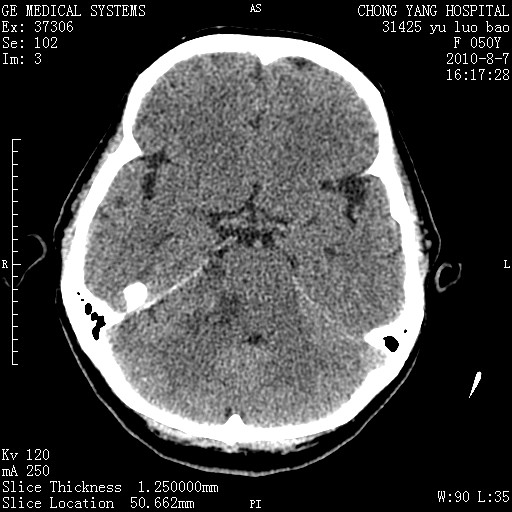

右侧桥小脑角区占位--听神经瘤,建议增强或mri检查。

右侧桥小脑角去等密度占位,右侧内听道扩大、骨质吸收,考虑:右侧听神经瘤,建议增强检查。

右侧内听道扩大、骨质吸收,中脑受压左移,考虑:右侧听神经瘤,建议增强检查。支持!

考虑右侧听神经瘤。